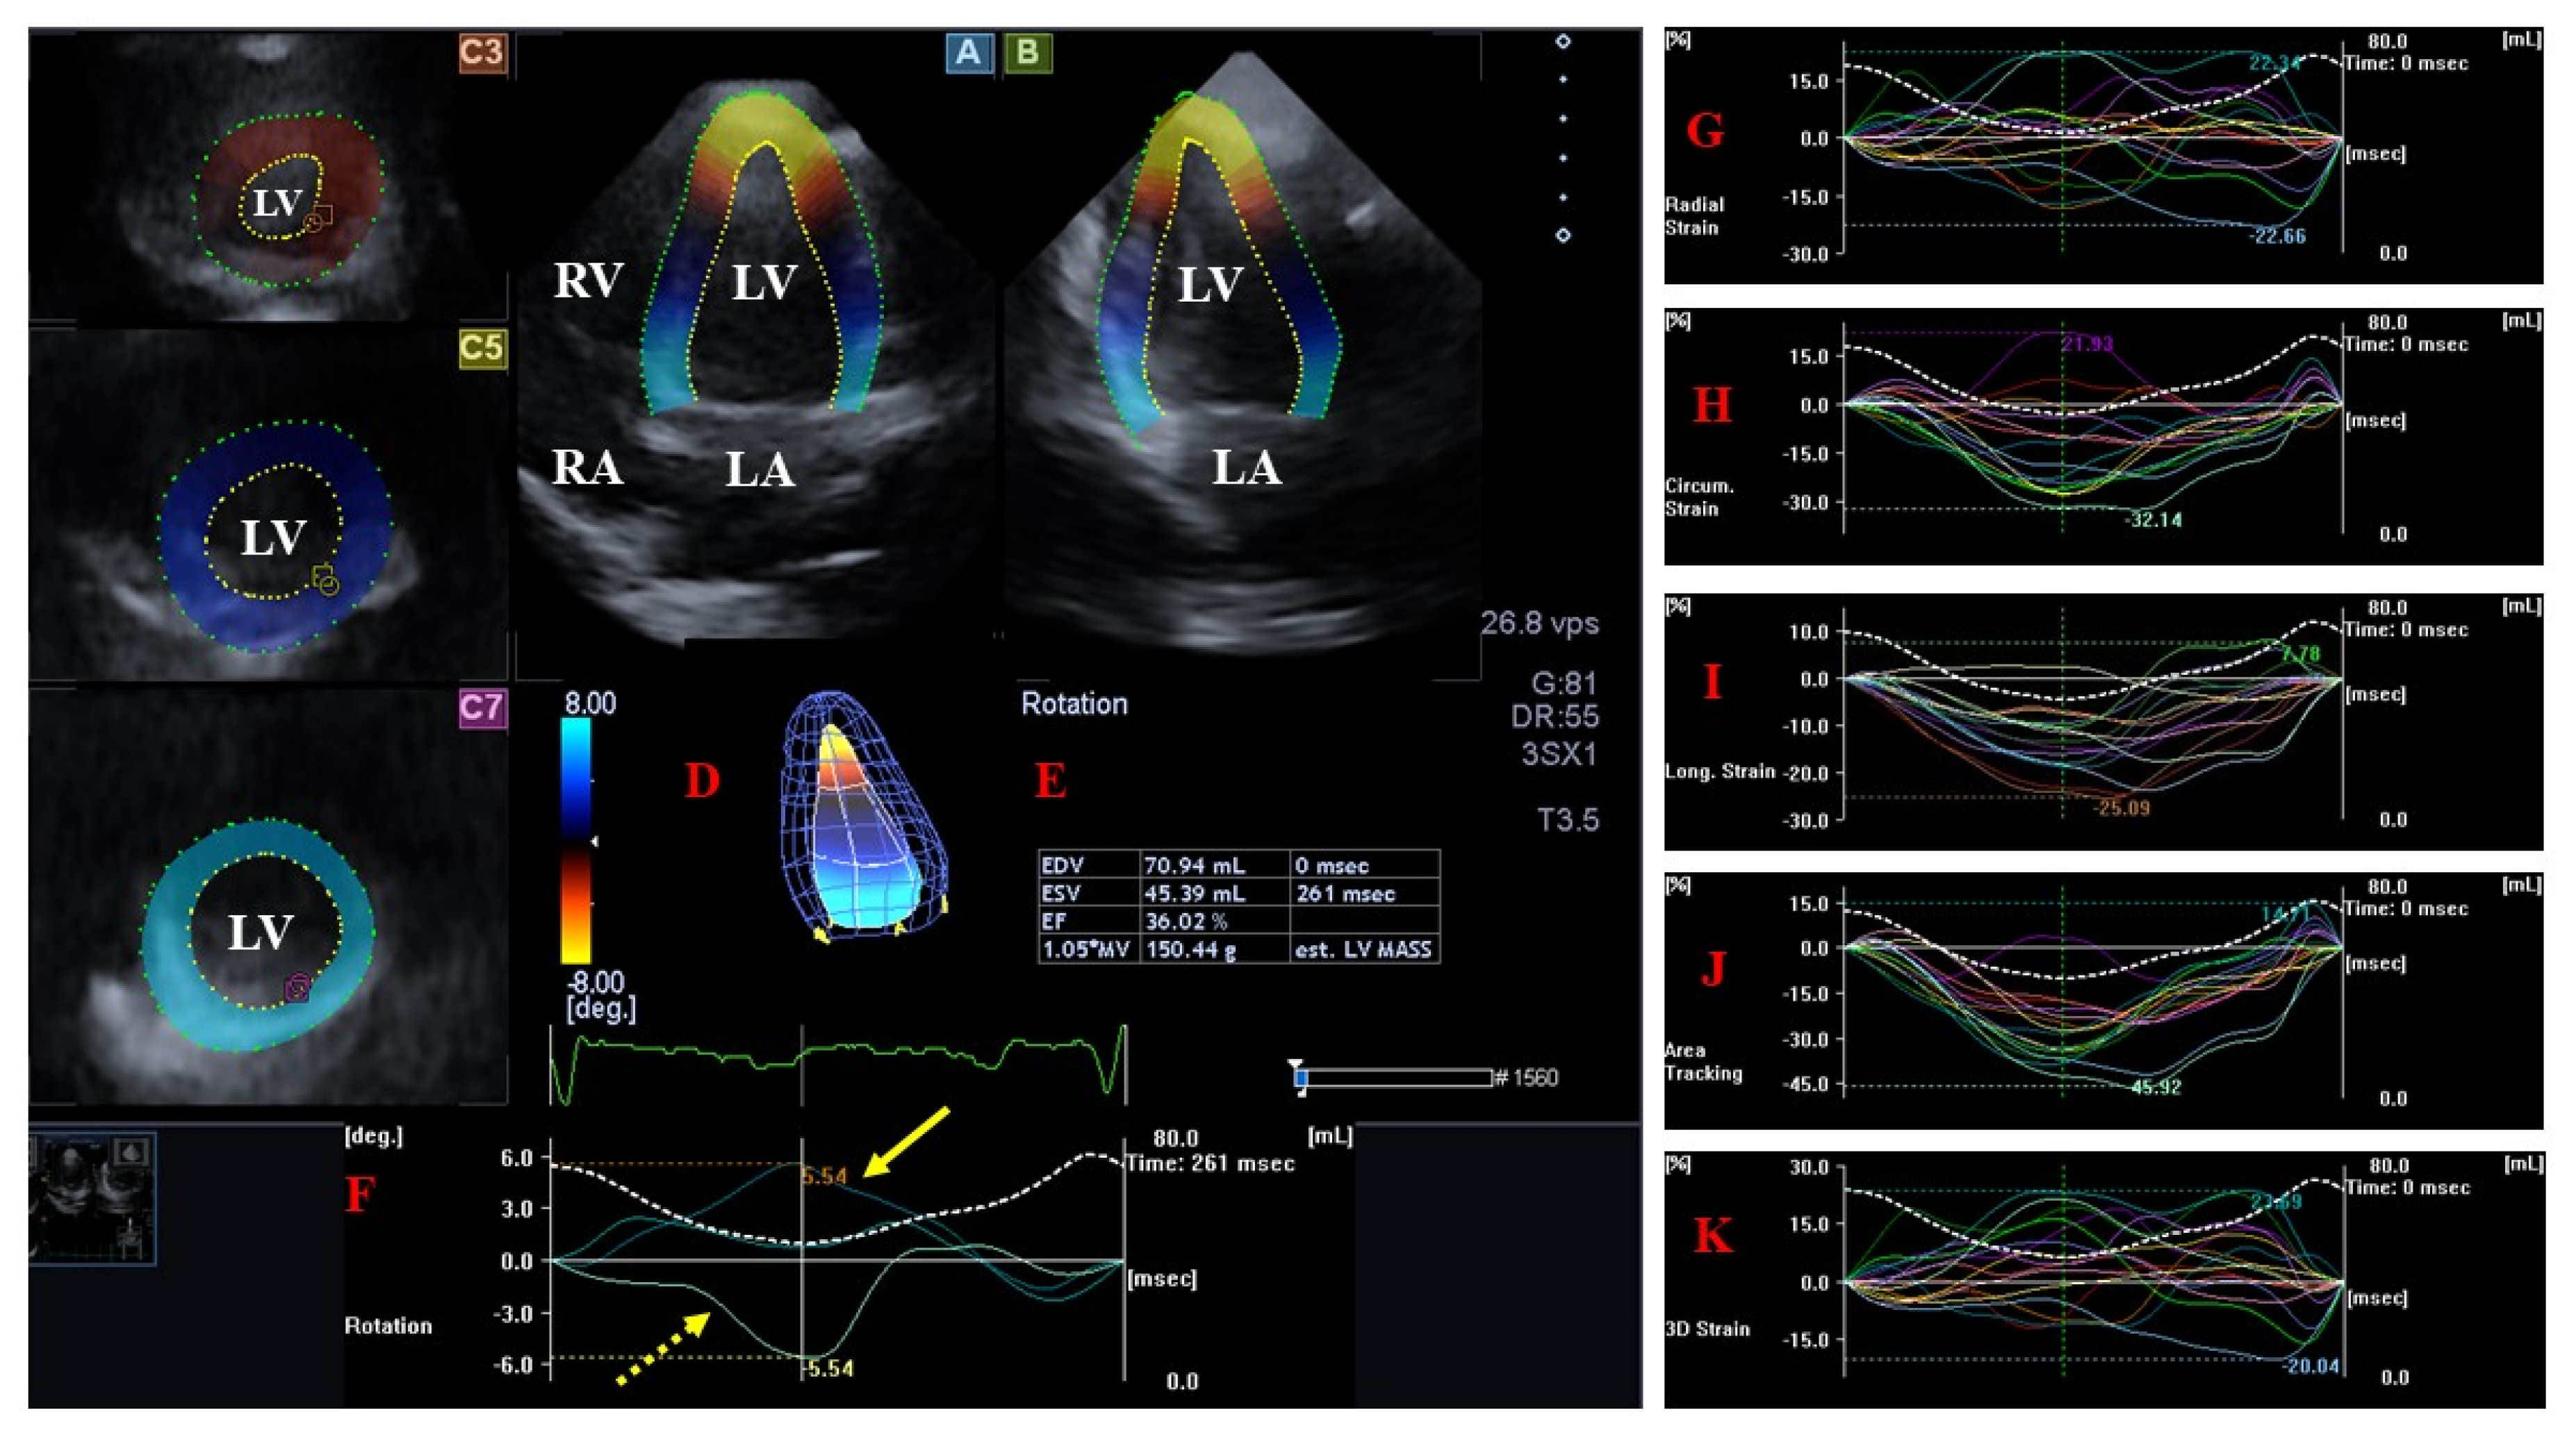

| All LV strains were decreased in all segments and LV-RS and LV-3DS showed further reduction in noncompacted segments compared to compacted segments. | [22] * | 9 | |

| LV twist was reduced. | [72] | 47 | |

| There was a decreasing pattern in LV rotation values in patients’ relatives. | [53] | 32 pts and 30 relatives | |

| LV-RBR had high specificity and sensitivity in differentiating NCCM from LV hypertrabeculation. | [75] | 52 pts with hypertrabeculation from which 34 proved to be NCCM | |

| Patients with LV-RBR showed worse NYHA functional status. | [73] | 60 | |

| Patients with lower LV-EF had higher rates of LV-RBR. | [47] | 31 | |

| Patients with clockwise LV-RBR had lower LV-LS but similar LV-EF. | [76] | 28 | |

| LV-RBR was present in 26–100% of patients and in most cases was oriented clockwise. | [74] | 10 | |